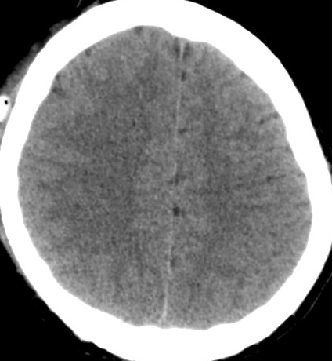

2014-10-5 CT